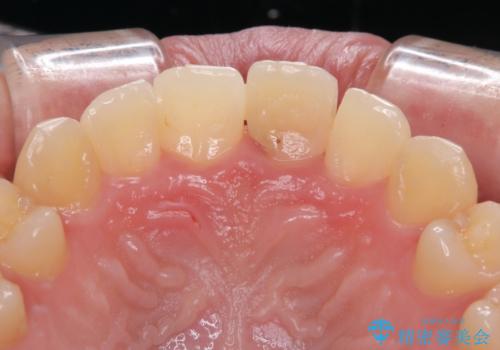

- 前歯のインプラント治療を希望して来院された患者様です。

小学生の時に前歯を殴打したとのことで、歯根が吸収してしまい、抜歯が必要と判断されました。

抜歯、インプラント埋入、仮歯の装着が同時に可能な1DAYインプラントを行いたいところでしたが、吸収による歯肉の炎症が著しいため、抜歯後に炎症が治まるまで待機し、極力早期にインプラント埋入を行うこととしました。